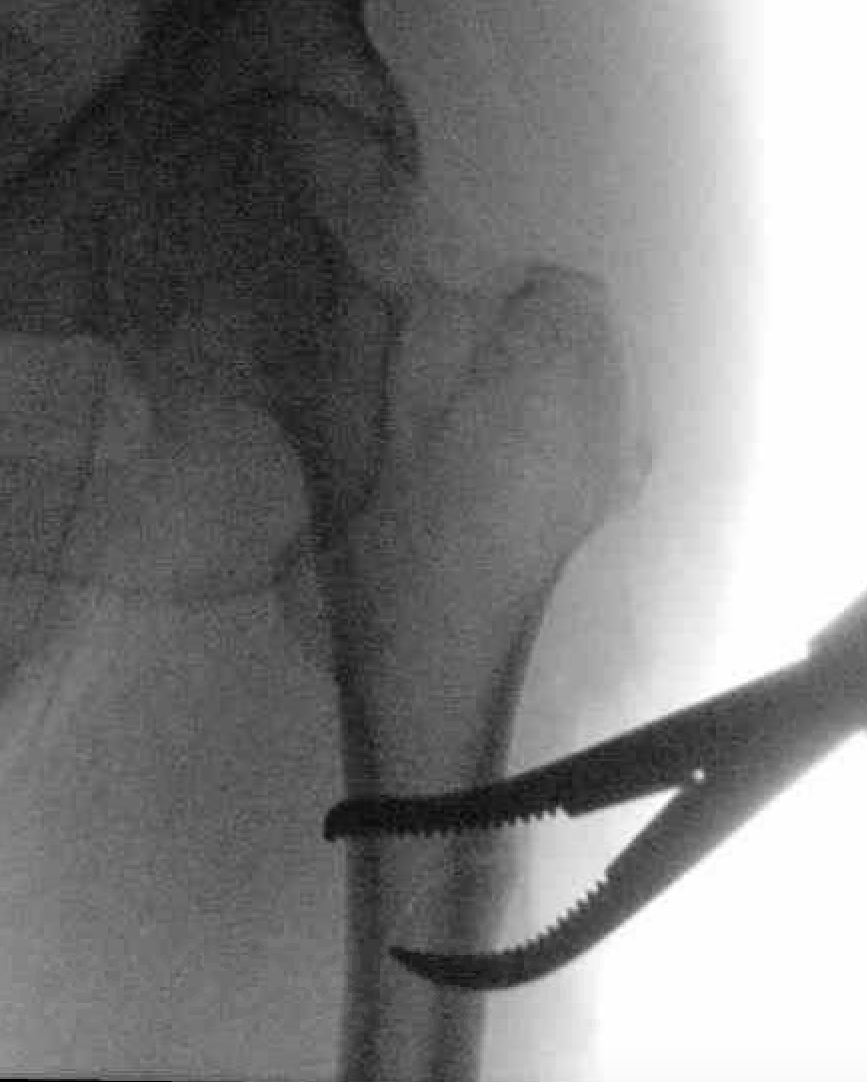

1. Proximal fragment flexed, in varus and externally rotated with distal fragment adducted

- iliopsoas flexes proximal fragment

- abductors cause varus of proximal fragment

- external rotators rotate proximal fragment

- adductors medialize distal fragment